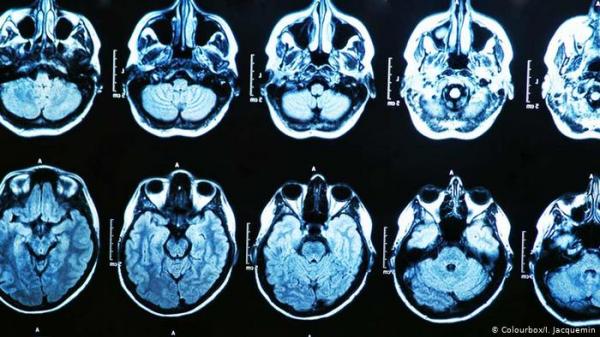

هل لوظائف المخ دور في الاختلاف بين الليبراليين والمحافظين؟